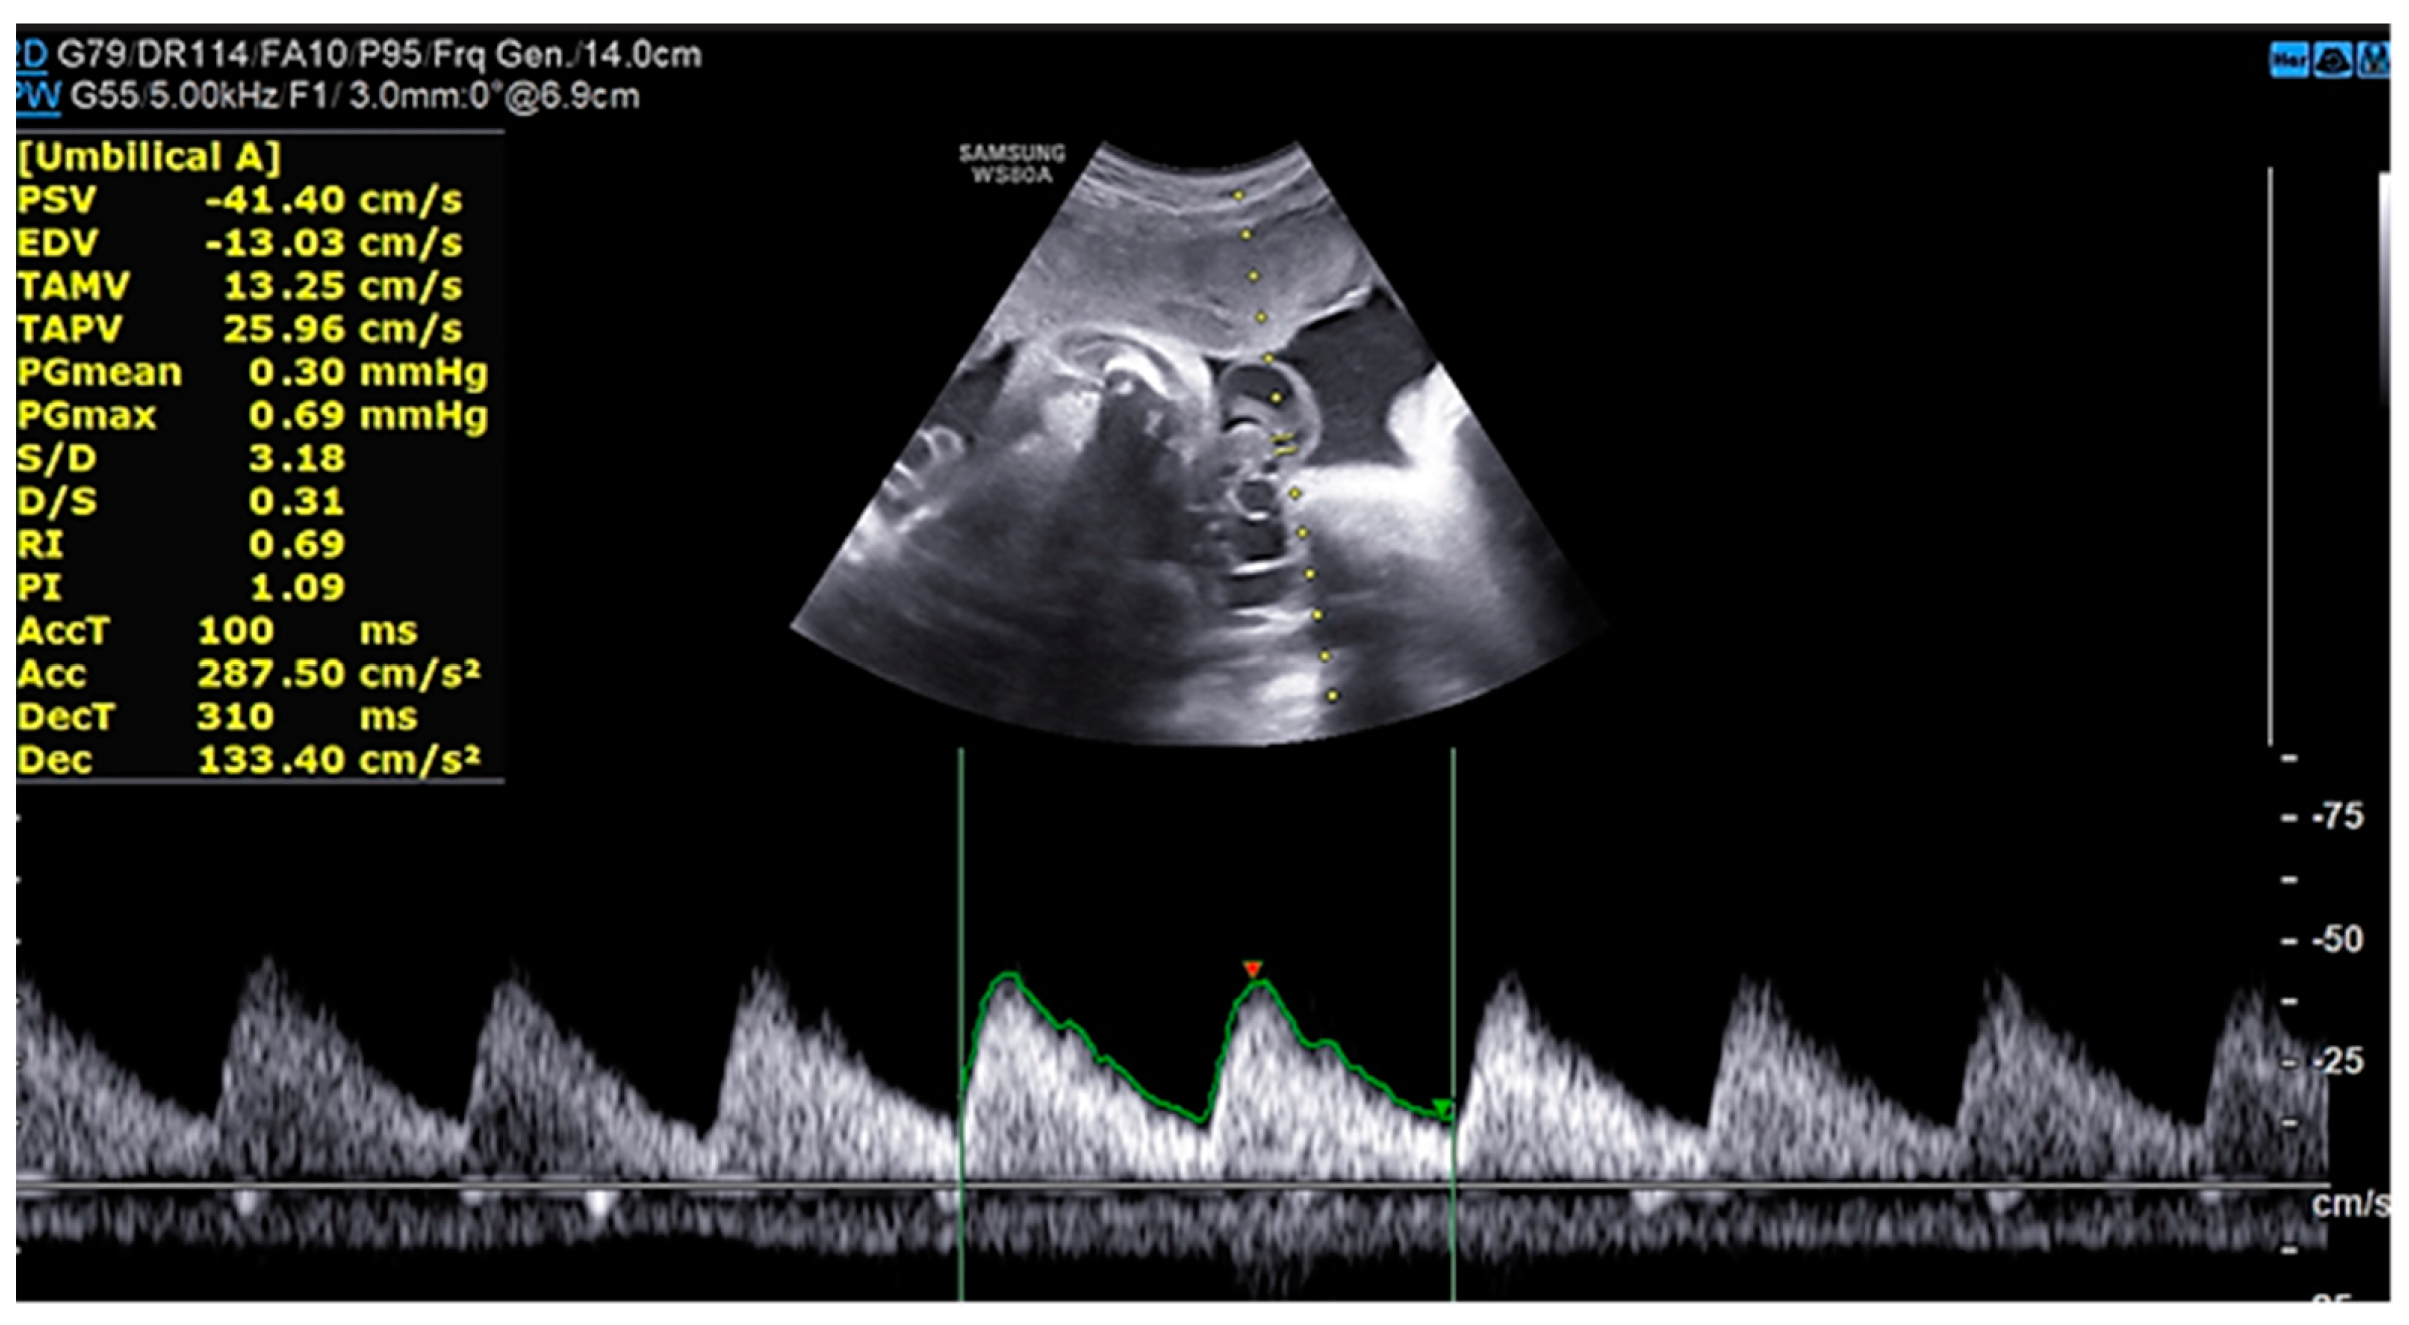

Percutaneous coronary intervention was therefore considered appropriate and a purposely undersized EBU 3.0 6F was selected. A safety wire, Runthrough floppy, was immediately placed on the patent left circumflex artery whilst after failing wiring on the left anterior descending with a Balance Middleweight wire a Sion wire was advanced up to the apical LAD. An IVUS run confirmed distal true lumen wire position showing a short subintimal track without compromise of any major side branch. (Figure 4, Figure 5, Figure 6 and Figure 7)

Figure 6. IVUS showing distal true lumen.